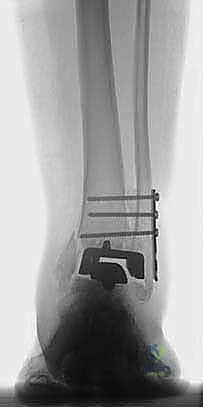

- Plain Radiographs: These are your first line. Malleolar fractures can be subtle or obvious.

- Obvious Fractures: Visible at the level of the prosthesis, generally at its apex or superior corners. In iatrogenic cases, they often occur at the superior saw cut line on the tibia, where the sagittal saw may have violated the malleolus. Significant distraction during the index procedure on osteoporotic bone can create avulsion fractures.

- Subtle Fractures: Often delayed in appearance, presenting as periosteal reactions at the medial malleolus proximal to the prosthesis. These typically indicate an unbalanced prosthesis placing uneven load or compression across the malleoli.

- Intraoperative Fluoroscopy: Essential for real-time guidance during fixation, but not for initial diagnosis of delayed fractures.